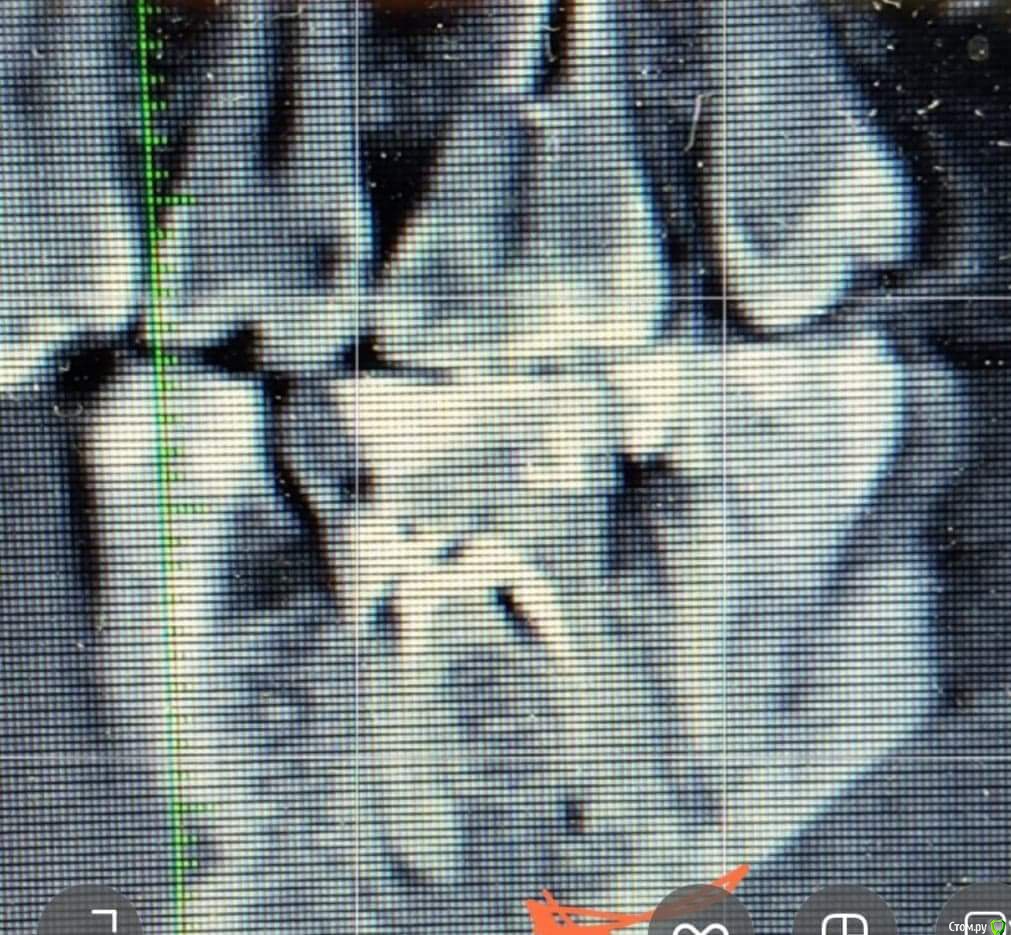

martynyukm Опубликовано 6 августа, 2018 Автор Поделиться Опубликовано 6 августа, 2018 Вот еще снимок Ссылка на комментарий

martynyukm Опубликовано 6 августа, 2018 Поделиться Опубликовано 6 августа, 2018 (изменено) Здраствуйте,один врач (хирург)сказал вырвать зуб,обьяснив,что он уже мертв и его не спасти. Боль иногда бывает,но на данный момент нет. Другой врач стоматолог сказал,что вырвать всегда успеешь,что лучше подождать. Хирург обьяснил по снимку,что под ним черные точки и как-то он может повлиять на соседний зуб,на котором у меня держится протез. Посоветуйте,пожалуйста,рвать или нет. Изменено 6 августа, 2018 пользователем martynyukm Ссылка на комментарий

Бендер Опубликовано 6 августа, 2018 Поделиться Опубликовано 6 августа, 2018 Выглядит вполне лечибельно. Перелом давно был? Ссылка на комментарий